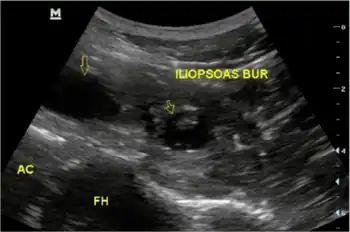

| a,b) Enhanced axial computed tomography of right iliopsoas bursitis and ultrasound-guided drainage | |

Iliopsoas bursitis is inflammation of a bursa (synovial sac) lying between iliopsoas muscle and hip joint, lateral to femoral vessels.[1] Pain is experienced over the same area and made worse by extension of hip joint.